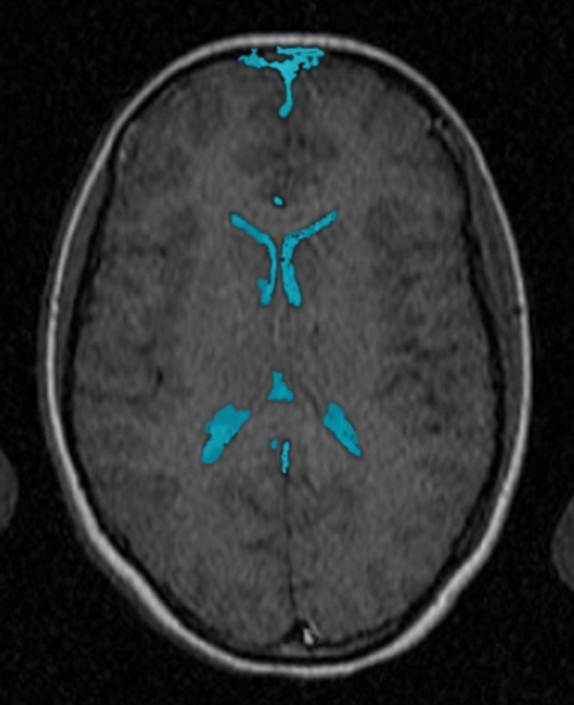

CT: Brain Atrophy

10 Years-Normal Gyri             65 Years-Enlarged Gyri